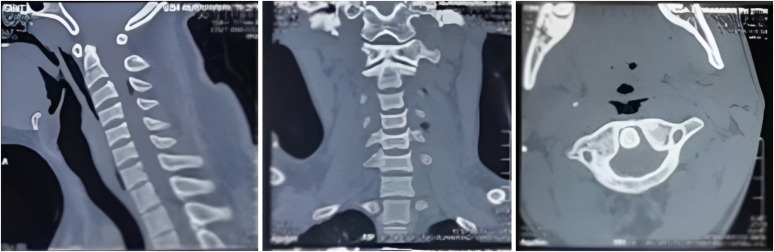

颈部穿透伤虽然罕见,但会造成严重后果,死亡率也很高。木质异物造成的颈椎损伤会增加感染并发症的风险。在本病例中,一名 27 岁的男性患者颈部受伤,显示为木质异物造成的穿透伤。计算机断层扫描(CT)显示没有颅内出血或骨折的迹象。此外,颈椎 CT 扫描也没有发现颈椎冠状肌或领长肌病变。医疗小组建议进行颈椎磁共振成像(MRI)检查,但患者家属拒绝了。随后,患者接受了伤口清创术,取出了一块刺入的木头碎片。术后两天,患者发烧,同侧肩臂无力。经过再教育,家属同意进行核磁共振成像检查。随后,根据核磁共振成像结果和临床表现对患者进行了手术治疗。残留的木质碎片被有效取出,患者的病情得到了积极的改善。

Although rare, penetrating neck injuries can have grave consequences, and are associated with high mortality rates. Individuals with cervical injuries due to wooden foreign bodies are at an increased risk of developing infectious complications. In this case, a male patient aged 27 years presented with a cervical injury indicative of a penetrating wound caused by a wooden foreign body. Computed tomography (CT) scan revealed no signs of intracranial hemorrhage or fracture. Additionally, cervical CT scan showed no evidence of cervical corpus or longus colli muscle lesions. The medical team suggested a cervical magnetic resonance imaging (MRI) examination; however, the patient's family opted out. Subsequently, the patient underwent wound debridement, which involved the extraction of a fragment of impaling wood. Two days after the procedure, the patient developed a fever and weakness of the shoulder and arm on the ipsilateral side. Following the process of re-education, the family provided consent for MRI examination. A subsequent surgical procedure was performed on the patient based on the MRI findings and clinical presentation. Residual wooden fragments were effectively extracted, resulting in positive progression of the patient's condition.